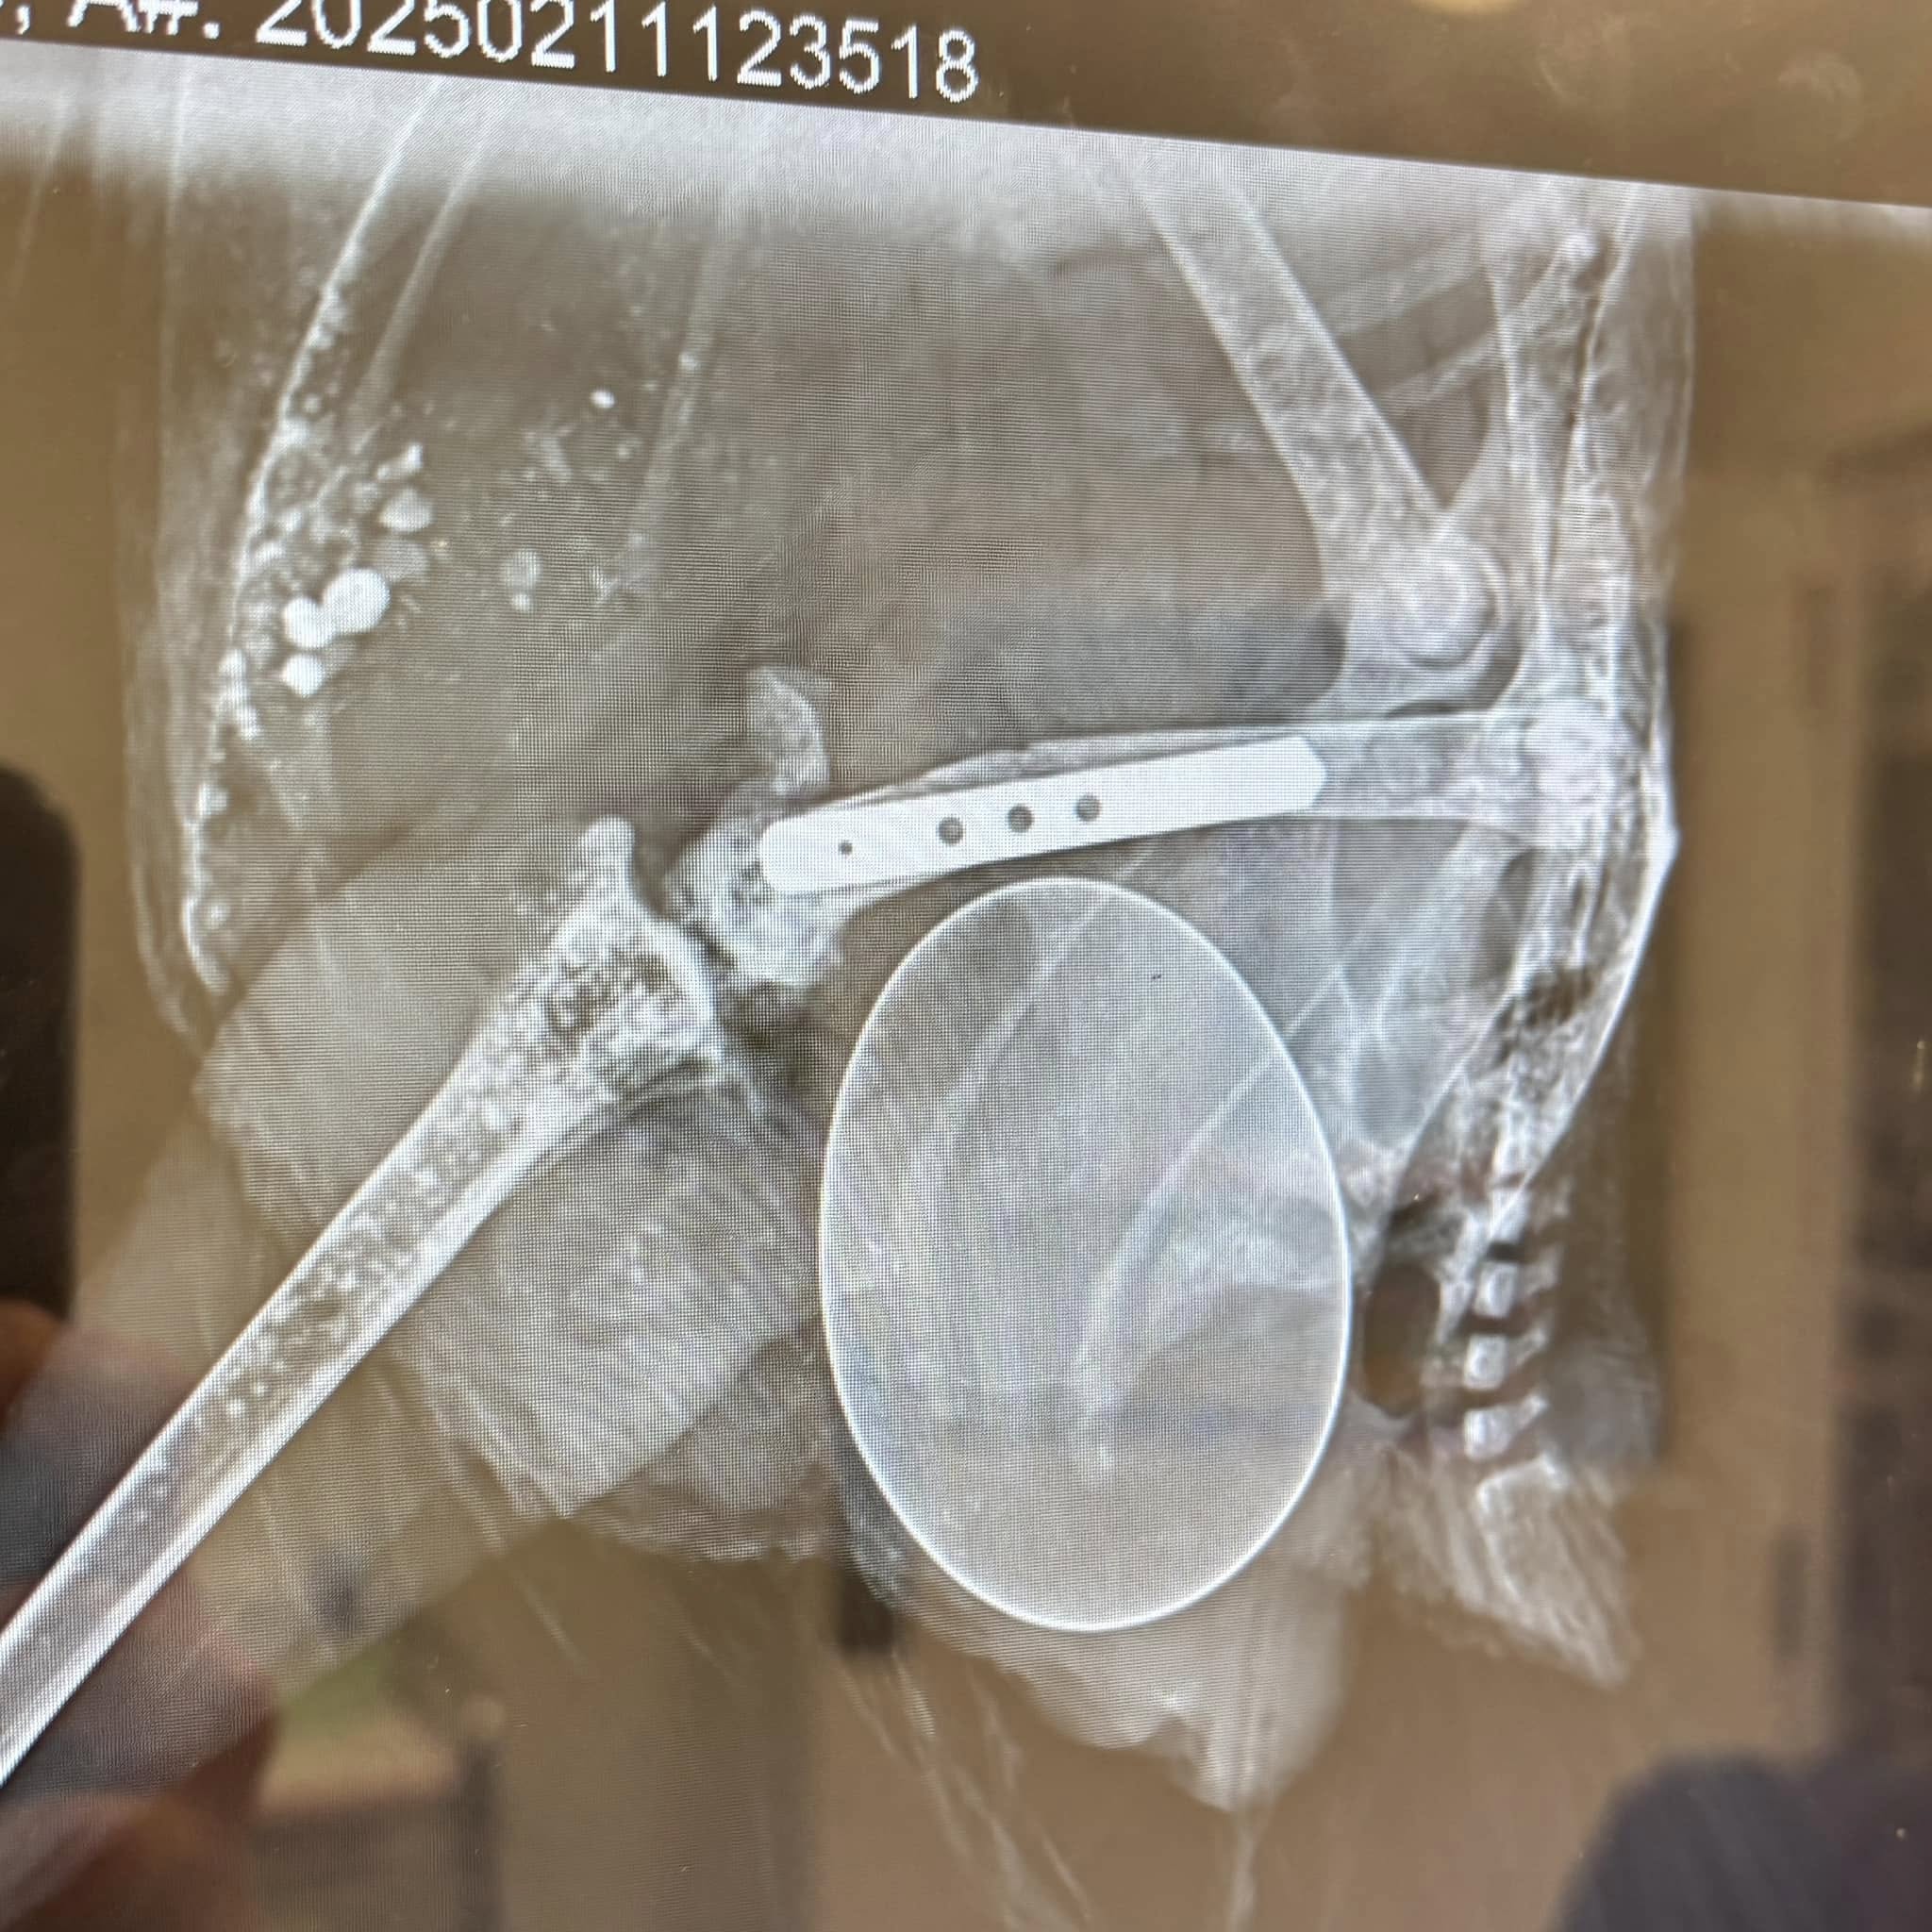

Little Dynamo Betty arrived here in early December and from the get go she was zipping around everywhere and pretending she was tough. She integrated in to the flock fine and all has been well. Last week, Dynamo decided to challenge Young Einstein, my big serious Isa, and Young Einstein retaliated and delivered one shocking kick that completely broke her leg bone. Shocked as I was I had to spring in to action, well it was my volunteer, Sally, who sprung in to action. She organised Roaming Vet Surgeons and Vetcall Melbourne to help Dynamo and she and vet nurse Emma worked unpaid to assist the surgery. So bloody grateful I am for such help and support. Dr Tracey did and amazing job and Dynamo is up and eating a buffet this morning that includes that egg you can see in the x-ray.

Dynamo Betty broke her leg here in a freak accident when she was in a fight with another chicken last month. Surgery went great and she came home ready to heal. Sadly an x-ray a week later showed the plate had moved, also moving the bone position. So, I walked around with Dynamo with her leg in this position for weeks, even having her in a sling around my waist trying to give the bone more of a chance to heal. She is an uber active hen and all this has been so frustrating for her and she’s fed up. Last week she got vet clearance to be able to do more things and Friday sees her go in for another x-ray and fingers crossed we have a healing bone.

She had surgery on her broken leg on Feb 11. Due to the plate moving slightly, her healing has taken longer than normal but Friday’s x-ray showed that it’s finally formed a callous! Hallelujah! It’s been a long and frustrating journey for us both.